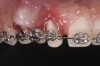

Tomographic images revealed a large tridimensional defect, with vertical and horizontal loss of bone extending to the apical third of teeth Nos. 6 and 8. Additionally, a buccal bone dehiscence was evident on tooth No. 5, and thin labial plates secondary to the orthodontic movement were present in several areas (Figure 3 and Figure 4).

Fig 3. Tomographic images revealed a tridimensional defect extending to the apical third of teeth Nos. 6 and 8, a buccal bone dehiscence on tooth No. 5, and associated thin labial plates.

Figure 3